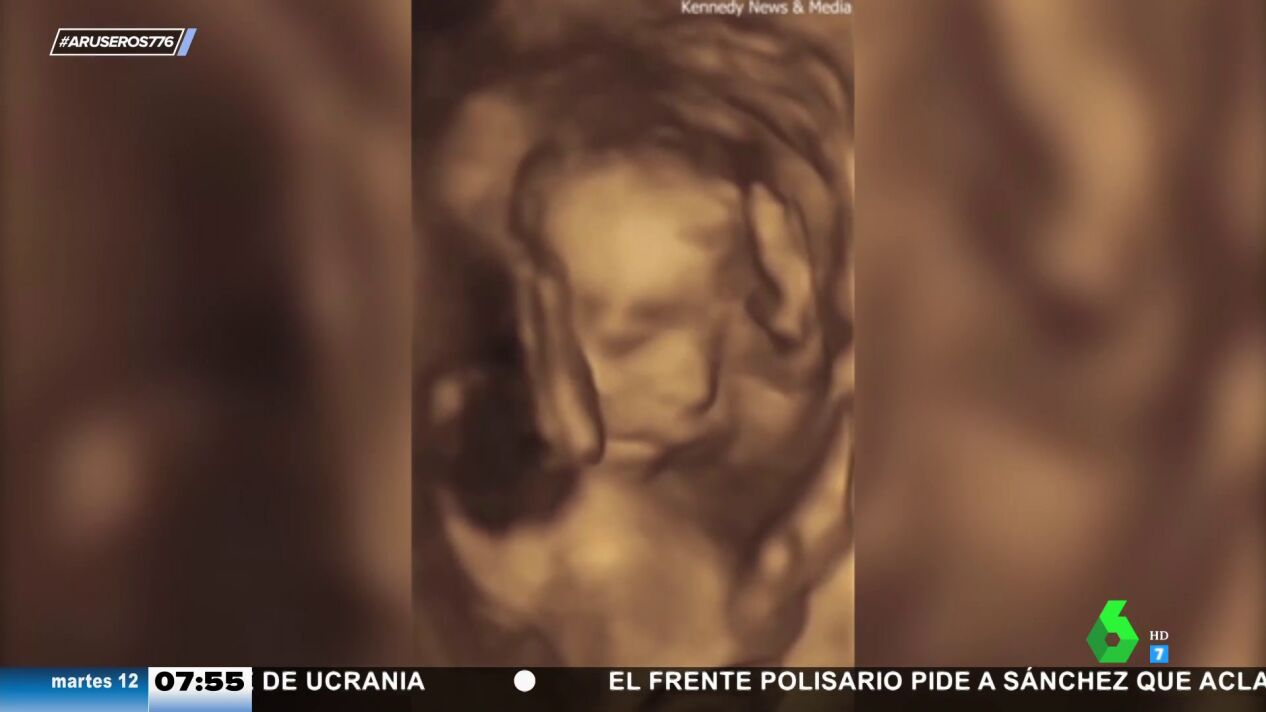

Aruser@s ha mostrado un sorprendente vídeo de una ecografía que ha compartido una madre de Pensilvania.

Las ecografías son un procedimiento rutinario al que las madres embarazadas deben someterse para comprobar el estado de su bebé. En ocasiones, los pequeños pueden moverse dentro del vientre de la madre, pero lo que se ha visto hoy en Aruser@s es del todo inusual.

En el vídeo que acompaña a la noticia, grabado por una madre de Pensilvania. se muestra una ecografía grabada en la que el bebé hace un claro gesto con la mano. "Se ha visto claramente que el bebé está haciendo una peineta", ha comentado Alfonso Arús. Por si no fuera suficiente, también ha hecho otro gesto más que ha sorprendido a los colaboradores de Aruser@s.